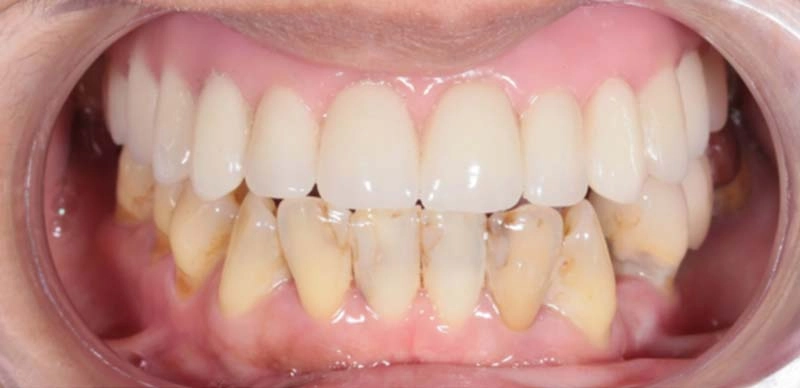

上顎牙橋鬆脫

all on 6全口修復牙齒外觀及功能